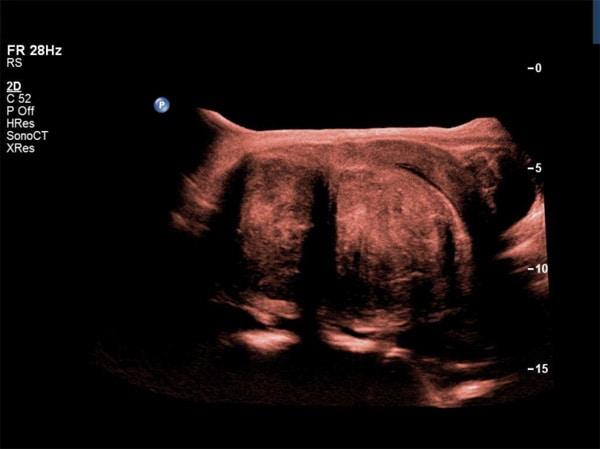

Learn how to sonographically evaluate uterine leiomyomas and adenomyosis, including their types, locations, and sonographic features. Explore diagnostic techniques like color Doppler and MRI, and understand treatment options such as myomectomy, hysterectomy, and uterine artery embolization for optimal patient care.